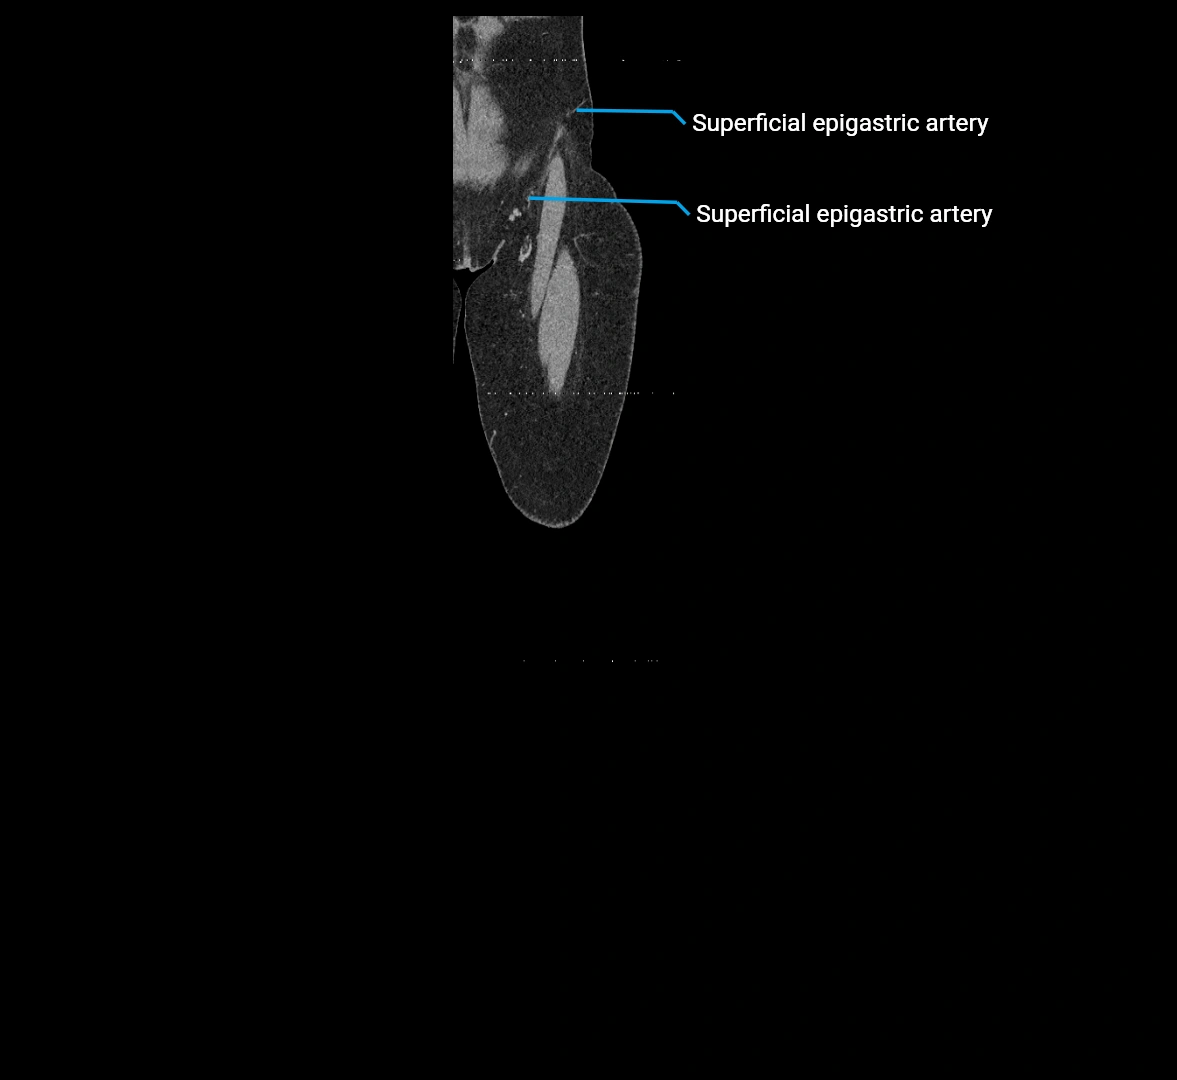

Contrast-enhanced CT (CTA):

• Gold standard for abdominal aortic imaging

• Provides excellent detail of lumen, wall, aneurysm, thrombus, and branch vessels

• Multiplanar and 3D reconstructions help in aneurysm measurement, stent graft planning, and dissection evaluation

• Detects acute rupture, traumatic injury, or occlusion with high sensitivity